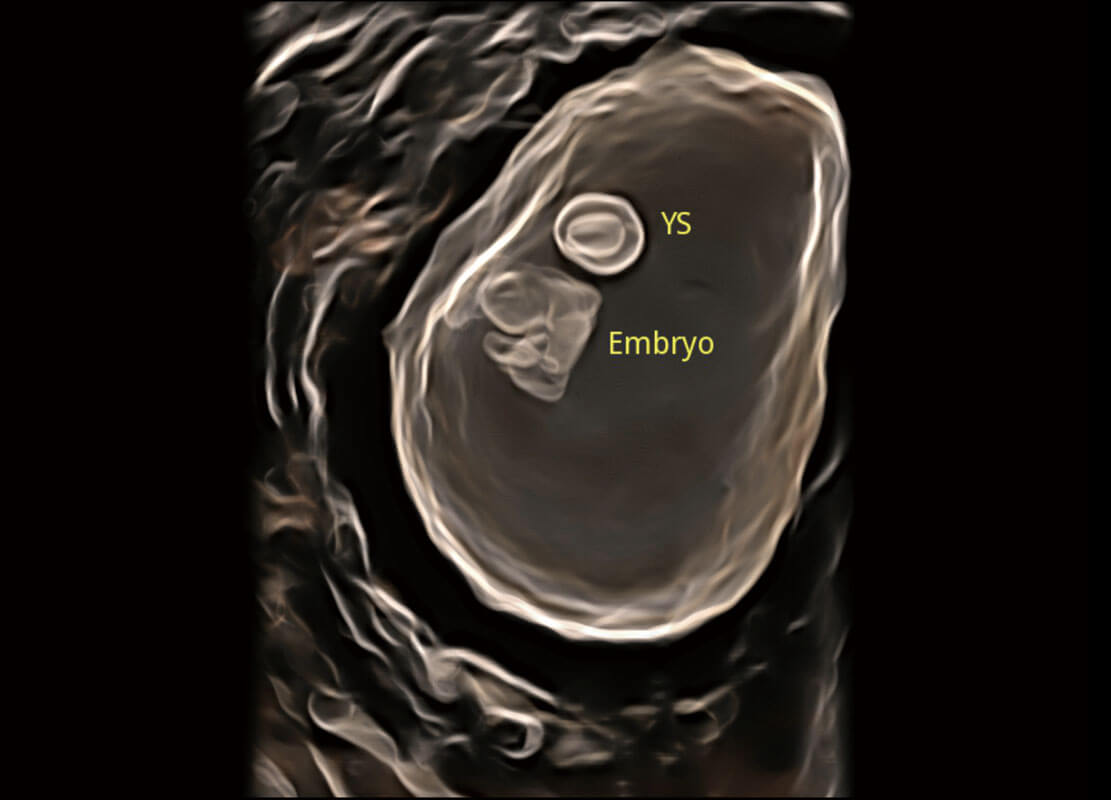

P60在胎儿早孕期超声筛查中为您带来优异的图像质量。

早孕-胎心

高分辨率容积成像-早孕胎儿

光影成像-孕囊